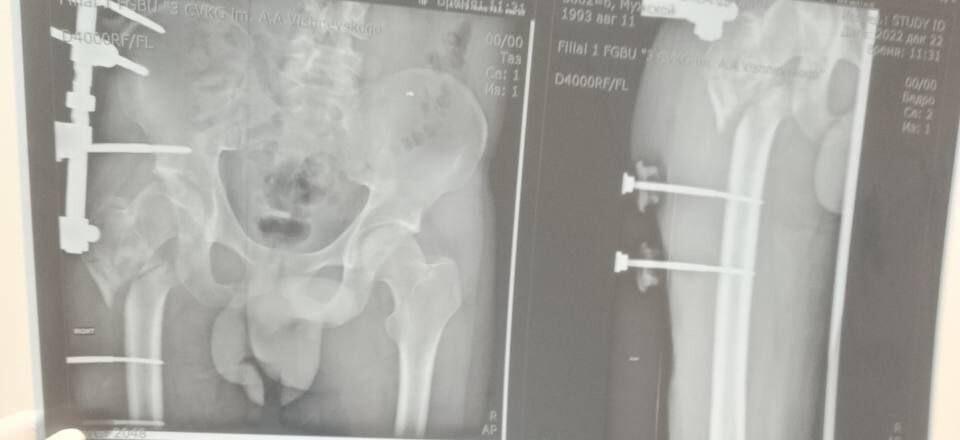

Руководитель Минздрава рассказала, что борьба с травмой сержанта из ЛНР длилась три с половиной года. За это время он проходил лечение в десяти госпиталях, в том числе в Москве и Санкт-Петербурге. В июле 2024 года военнослужащий, удостоенный медали «За отвагу», был уволен со службы по состоянию здоровья. Из-за обширных повреждений и многократных операций правая нога бойца стала короче левой на восемь-девять сантиметров. Обычное эндопротезирование изменить ситуацию не могло.

«Вместо стандартной замены сустава пациенту выполнили сложнейшее вмешательство с использованием ревизионных систем эндопротезирования, в ЛНР такую операцию провели впервые», — цитирует Пащенко ЛИЦ.

Она уточнила, что главная задача хирургов заключалась не просто в установке импланта, а в восстановлении биологической оси конечности и компенсации укорочения.